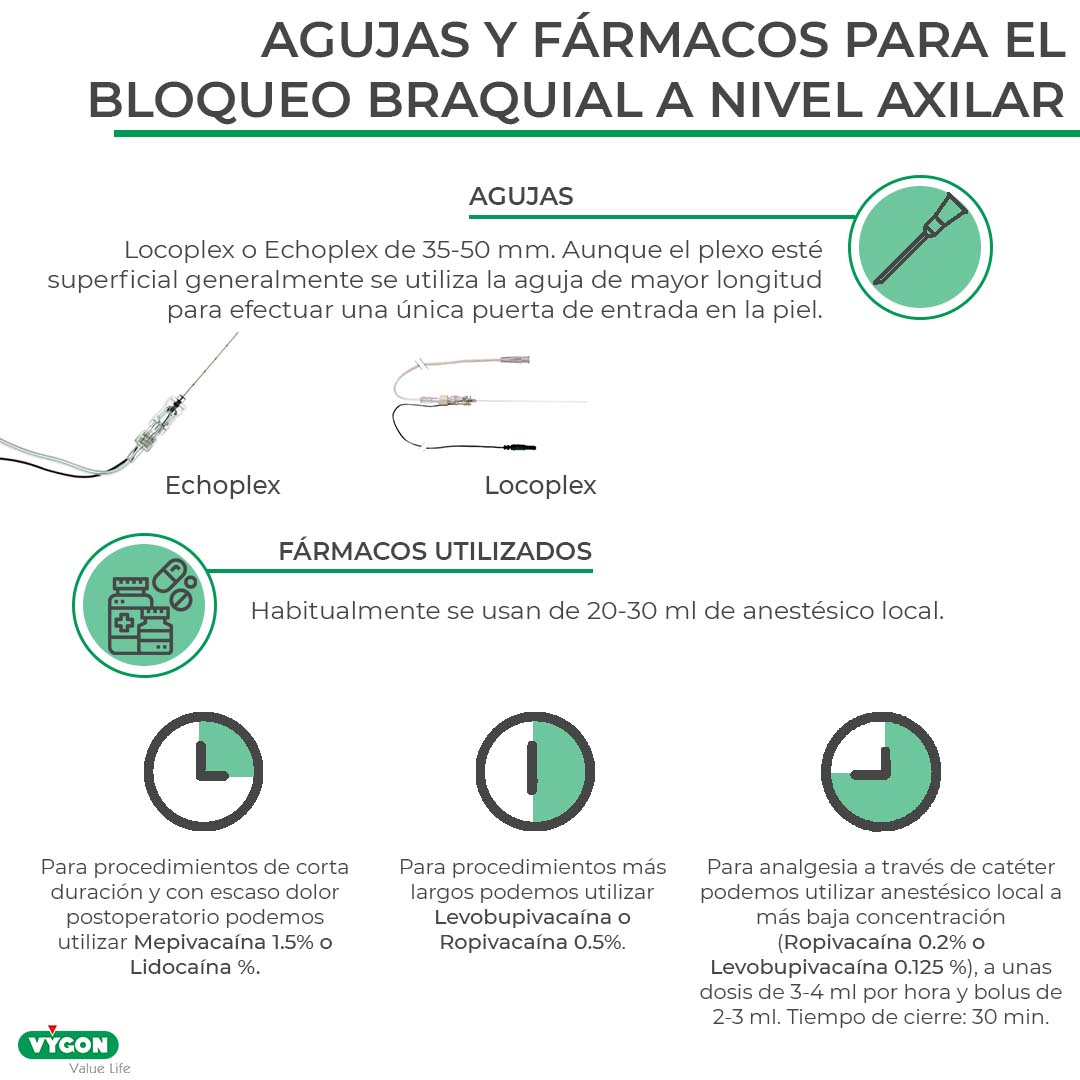

- Agujas: LocoplexÒ o EchoplexÒ de 35-50 mm. Aunque el plexo esté superficial generalmente se utiliza la aguja de mayor longitud para efectuar una única puerta de entrada en la piel.

- Fármacos utilizados. Habitualmente se usan de 20-30 ml de anestésico local. Para procedimientos de corta duración y con escaso dolor postoperatorio podemos utilizar Mepivacaína 1.5% o Lidocaína %. Para procedimientos más largos podemos utilizar Levobupivacaína o Ropivacaína 0.5%. Para uso como analgesia a través de catéteres (SilverstimÒ o MultiplexÒ) (Fig. 2) podemos utilizar anestésico local a más baja concentración (Ropivacaína 0.2% o Levobupivacaína 0.125 %), a unas dosis de 3-4 ml por hora y bolus de 2-3 ml con un tiempo de cierre de 30 minutos.

La colocación de catéteres a nivel axilar suele tener una alta incidencia de fallos por salida del catéter debido a la movilidad de la articulación glenohumeral.